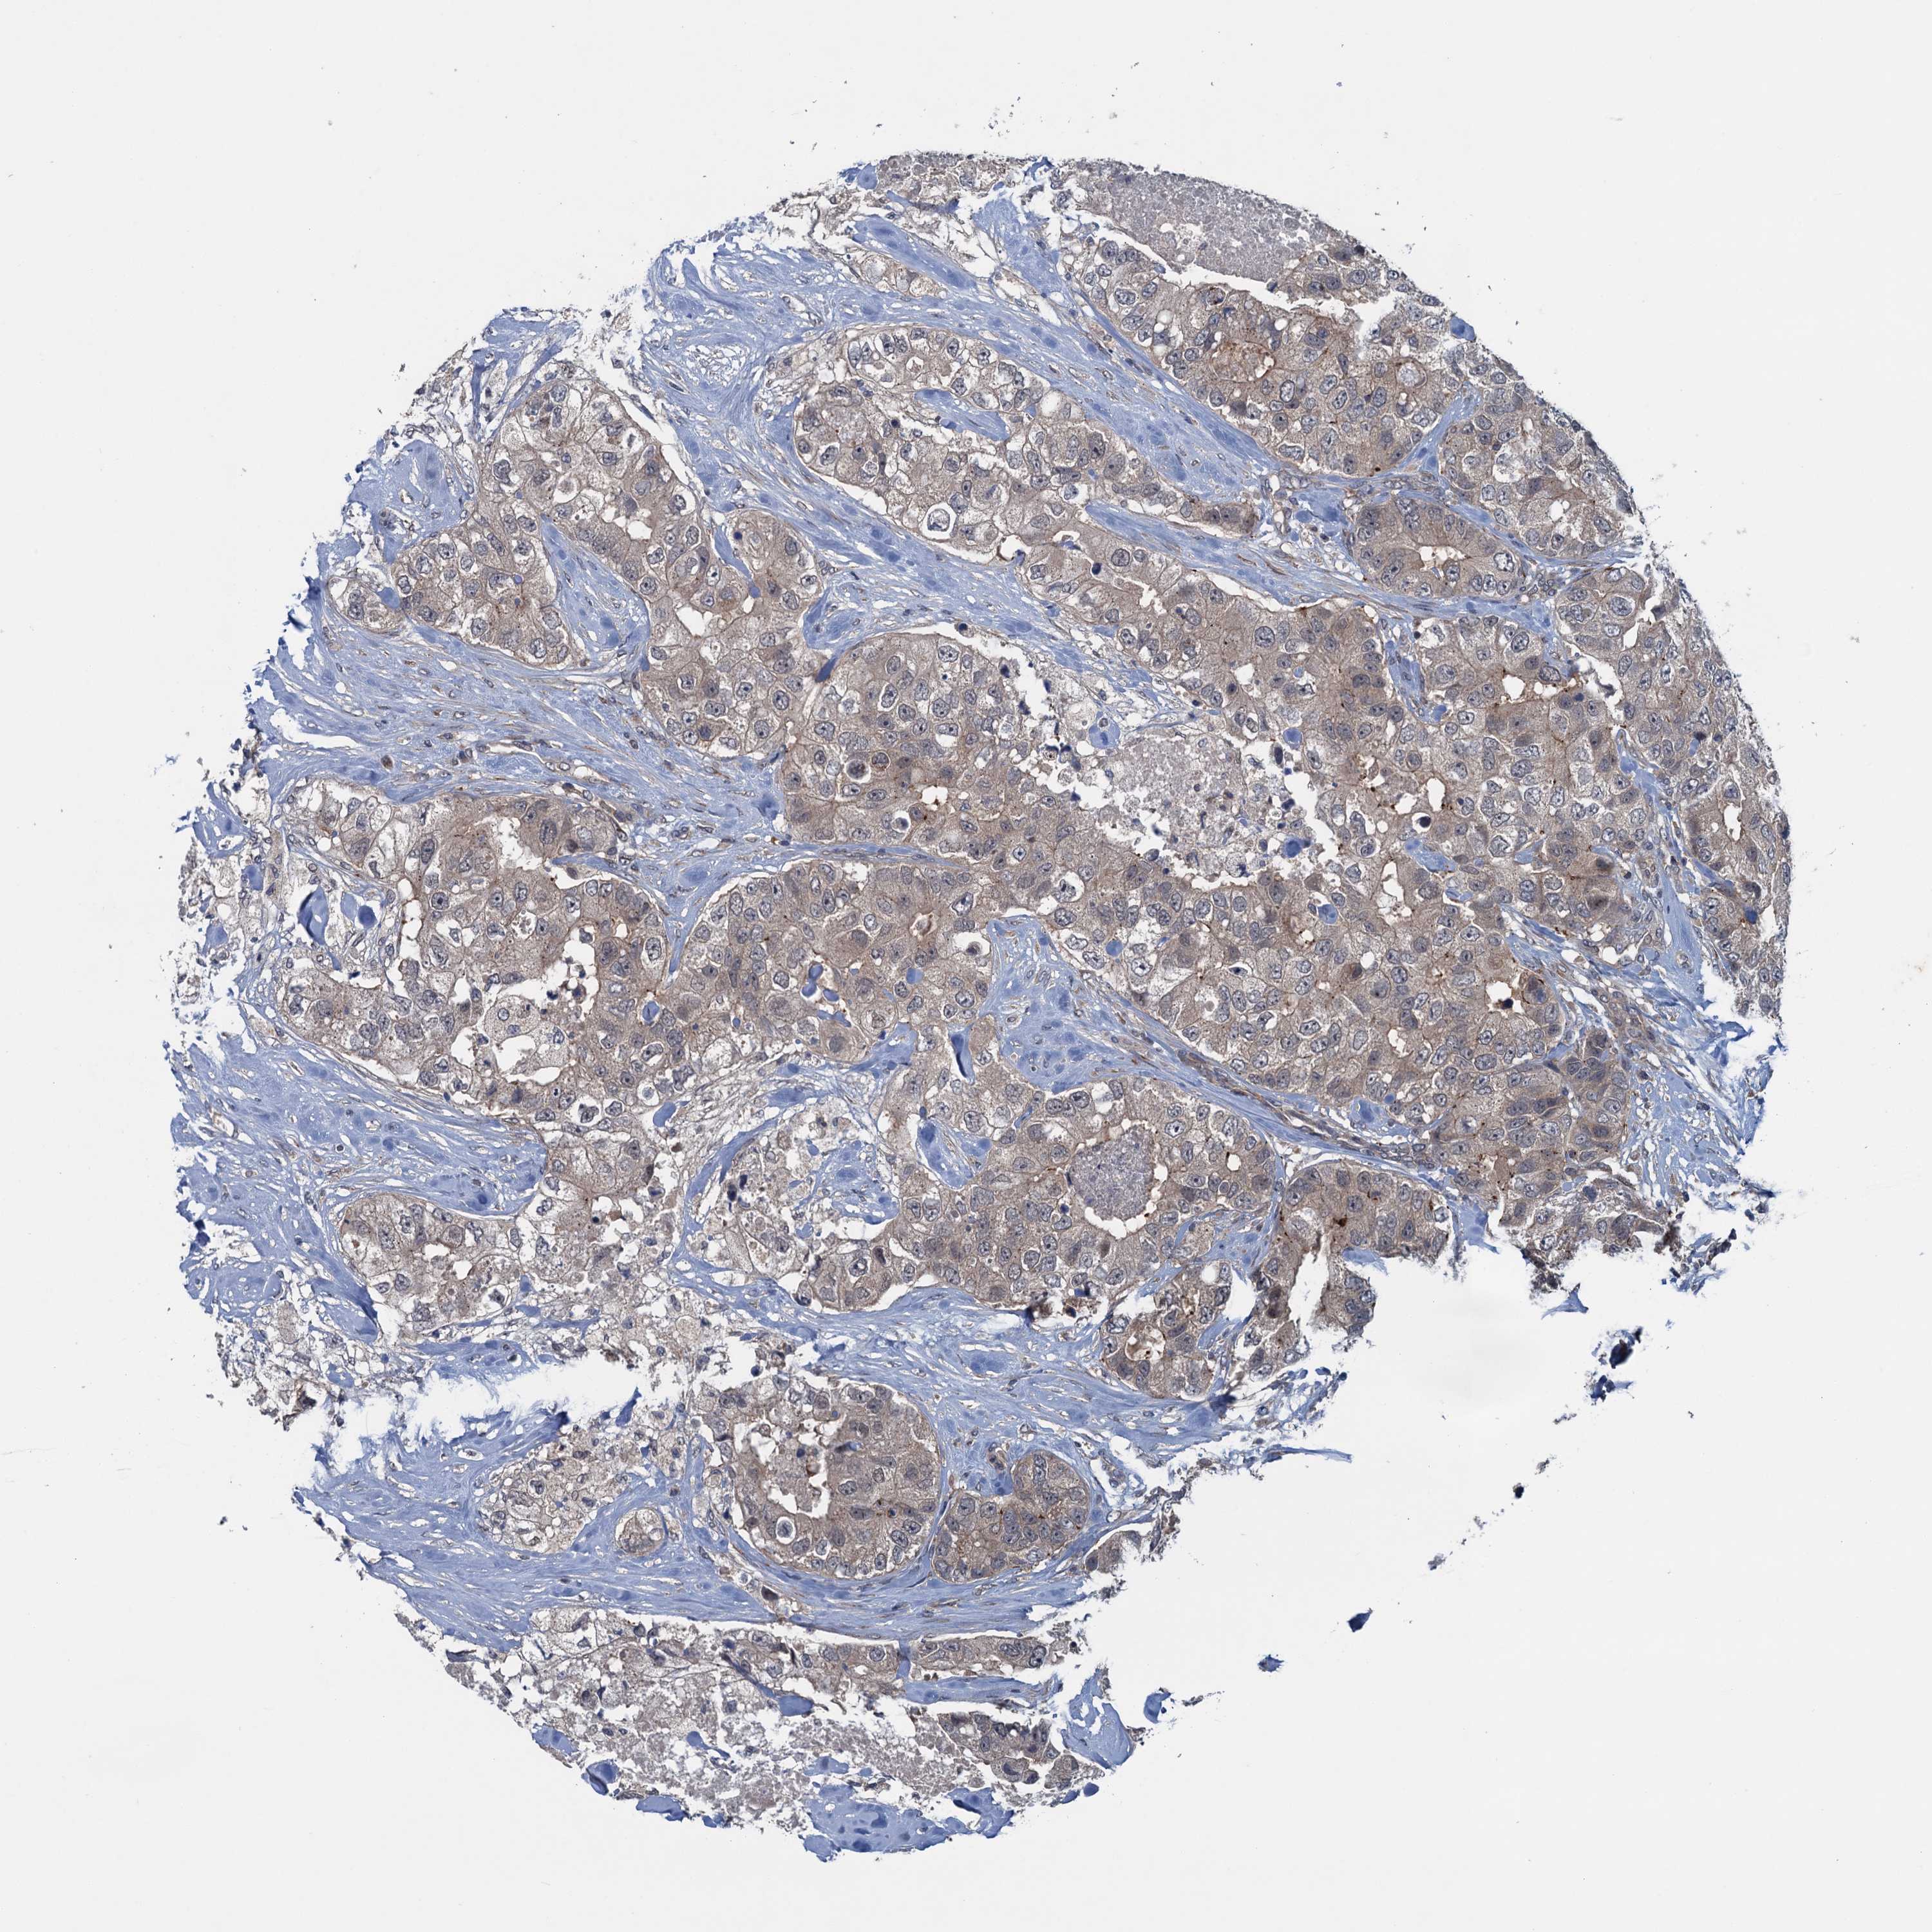

CANCER BREAST CANCER Show tissue menu

BRCA TCGA BRCA VALIDATION PROTEIN EXPRESSION